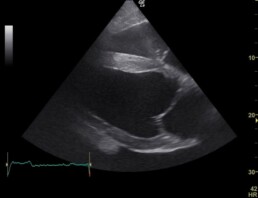

Es wurde eine mittelgradige Aortenklappeninsuffizienz festgestellt. (Abb. 1+2)

Abb.1: 4-Kammerblick rechts